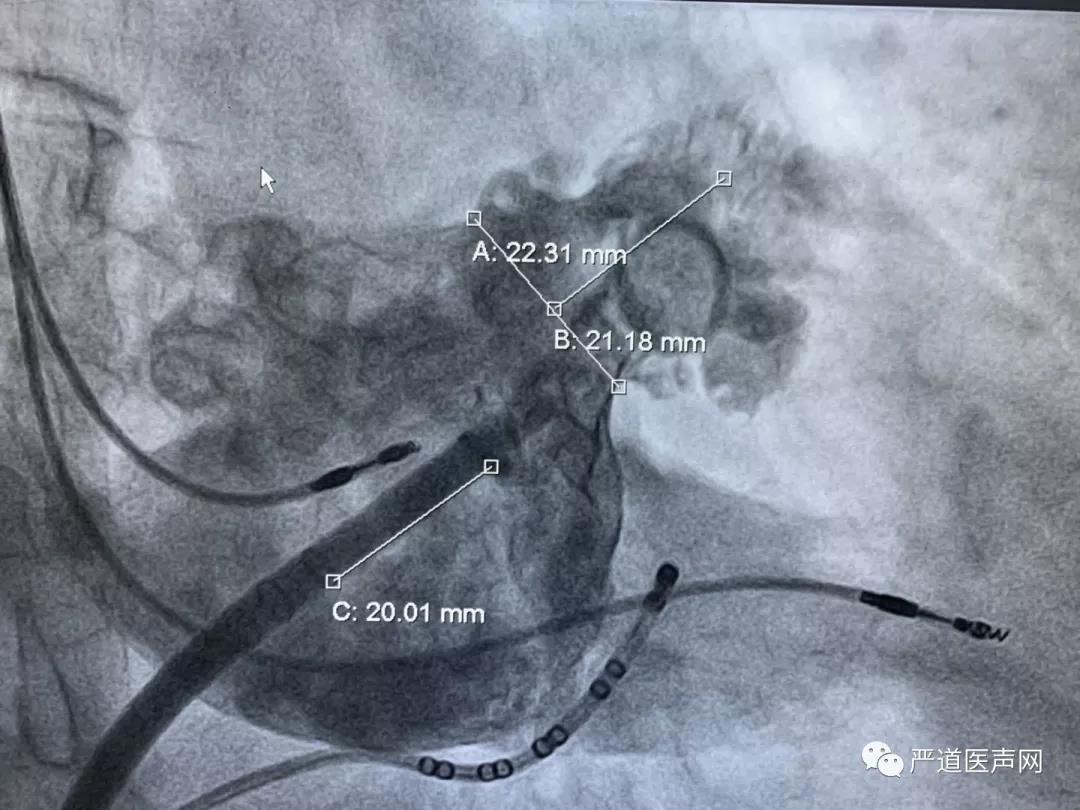

左心耳肝位造影

封堵伞展开后造影

、